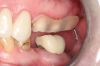

Fig 1. Preoperative surgery.

Figure 1

Fig 2. Extractions and immediate placement.

Figure 2

Figure 1 and Figure 2 depict the preoperative image and subsequent removal of three posterior teeth, immediate placement of zirconia-oxide ceramic dental implants, and soft-tissue augmentation with platelet-rich fibrin (PRF) to enhance the soft-tissue architecture surrounding the ceramic implants. The teeth were removed atraumatically and without suture placement. Because the implants were one-piece in stature (the abutment was incorporated into the implant), the recommendation was to splint the multiple units to minimize the lateral forces from mastication, swallowing, and tongue movement.